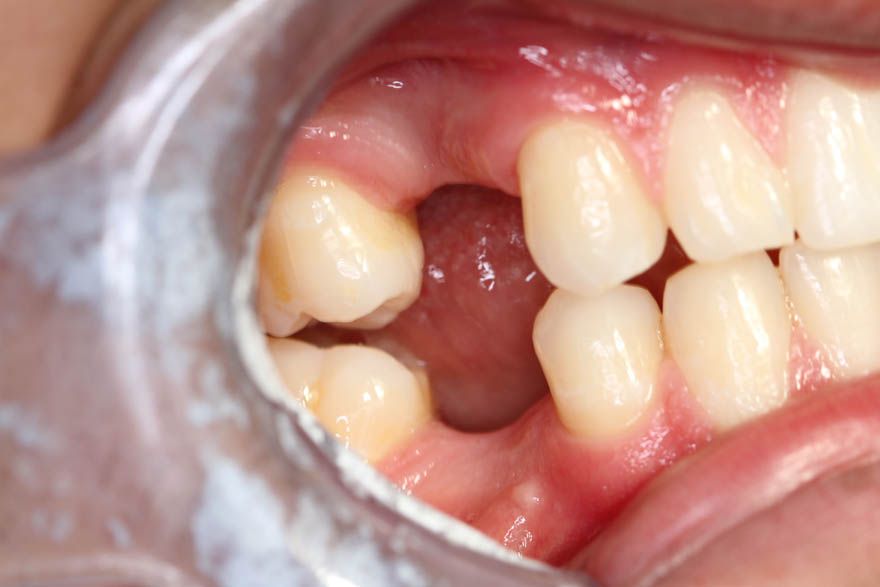

Initial situation: An 18-year-old patient was seen at our joint practice following completion of orthodontic treatment. For reasons of symmetry, the space was closed at premolar width with agenesis in regions 15, 14, 24, 25, 35 and 45. In region 46, tooth 46 was extracted at the age 15 years due to a deep cavity and the space closed orthodontically to premolar width. In the third quadrant, the interdental space in region 35 was closed due to mesialization of tooth 36. Following completion of orthodontic treatment with interdental spaces in regions 14, 24 and 44 and a desire for implantological treatment, the patient was seen at our practice (Fig. 1). The patient rejected alternative prosthetic treatment options including fixed one- or two-arm ceramic bridges. The patient had no relevant systemic diseases. Clinical findings: The oral hygiene of the patient at the time of initial presentation could be improved. Clinically, there was bone and soft tissue resorption in regions 14, 24 and 44 in both the vertical and horizontal dimension as observed in the agenesis with no prior orthodontic space closure. In regions 14 and 24, there was sufficient vertical bone due to anatomically distal displacement of the recess of the maxillary sinus. In preoperative planning, a vertical bone height of 18.6 mm was measured in region 44 up to the inferior alveolar canal, which was more than sufficient (Fig. 2). Based on the present clinical conditions and the young age of the patient, we decided for placement of ceramic implants.